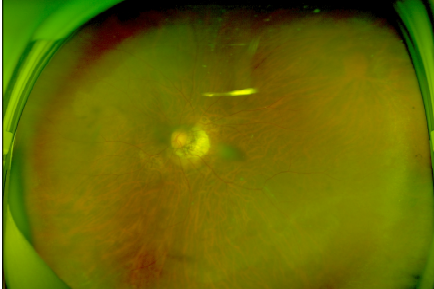

周阿姨的双眼术后眼底照片

经过半年的随访复查,周阿姨的双眼近视度数基本稳定。但深受高度近视折磨的周阿姨下定决心,要通过手术彻底摘掉这个跟随了自己几十年的眼镜。